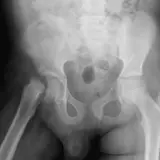

Casos totalmente interativos com as ferramentas que você espera em um PACS — rolagem, ajuste de janela, zoom, movimentação, medidas, ROIs e modo de tela cheia.

Anotações detalhadas destacam os achados principais diretamente nos casos. Clique nos achados vinculados nas descrições dos casos para ir ao local exato no exame.